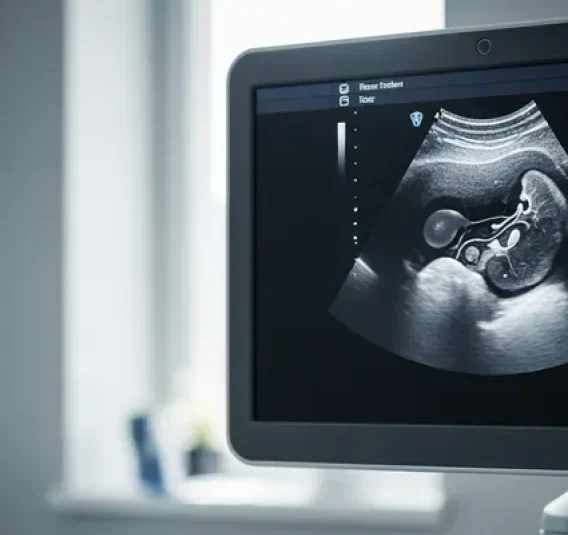

Reporting of focal liver masses in patients at risk (for example those with chronic liver disease) presents significant clinical challenges, particularly when using contrast-enhanced ultrasound (CEUS). The study aimed to evaluate an algorithmic, synoptic reporting approach that leverages the CEUS LI-RADS framework in high-risk patients.